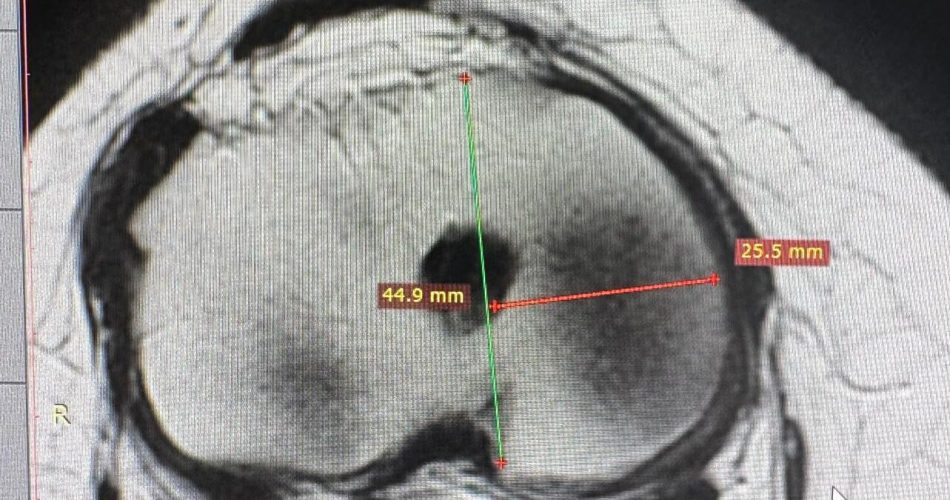

Misurazione e pianificazione per intervento menisco (2)

Eseguito per la prima volta nel Sud Italia un trapianto meniscale da donatore. L’intervento è stato realizzato al Policlinico di Bari, nella clinica ortopedica diretta dal prof. Giuseppe Solarino, da un’équipe composta dai chirurghi Lorenzo Moretti e Danilo Cassano. Si tratta di una procedura altamente specialistica, eseguita su una judoka professionista con una storia clinica complessa, già sottoposta a ricostruzione dei legamenti crociato anteriore e collaterale laterale e a una meniscectomia totale, che nel tempo aveva provocato dolore persistente e sovraccarico articolare del ginocchio.

L’intervento ha previsto l’impianto di un menisco da donatore, stabilizzato attraverso suture specifiche per garantire l’integrazione con le strutture articolari. Il trapianto meniscale consente di ripristinare la funzione biomeccanica del ginocchio, riducendo il rischio di degenerazione precoce dell’articolazione, soprattutto nei pazienti giovani e negli atleti. In Italia vengono eseguiti ogni anno circa 100mila interventi per lesioni meniscali, per lo più meniscectomie o riparazioni. Il trapianto meniscale resta invece una procedura complessa e riservata a centri specializzati. “La nostra clinica si conferma un punto di riferimento nazionale nell’applicazione delle tecnologie più avanzate”, ha dichiarato Solarino, sottolineando l’impegno nella chirurgia ortopedica ricostruttiva e nella traumatologia sportiva.